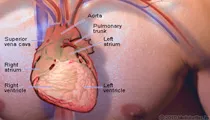

Heart Anatomy

View an illustration of the heart and see more medical anatomy and illustrations.

Heart Anatomy: Diagram, Blood Flow and Functions

Heart Anatomy: Diagram, Blood Flow and FunctionsThe heart is a very important organ in the body. It is responsible for continuously pumping oxygen and nutrient-rich blood throughout your body to sustain life. It is a fist-sized muscle that beats (expands and contracts) 100,000 times per day, pumping a total of five or six quarts of blood each minute, or about 2,000 gallons per day.

Picture of Heart

Picture of HeartThe muscle that pumps blood received from veins into arteries throughout the body. See a picture of the Heart and learn more about the health topic.

Picture of Heart Detail

Picture of Heart DetailThe heart is composed of specialized cardiac muscle, and it is four-chambered, with a right atrium and ventricle, and an anatomically separate left atrium and ventricle. See a picture of Heart Detail and learn more about the health topic.